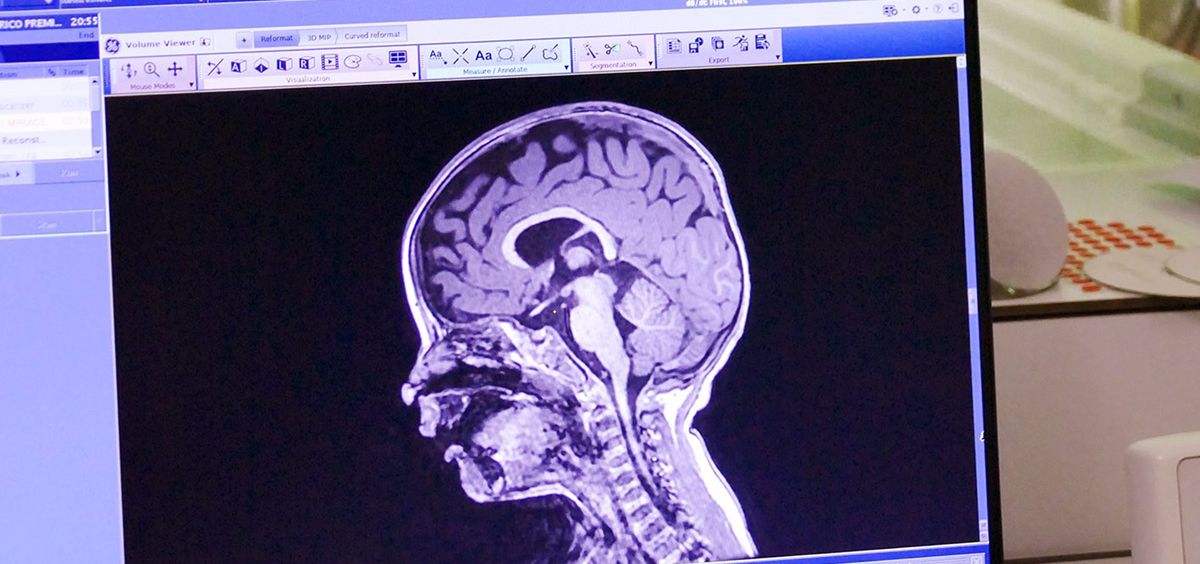

Hospital Universitario Quirónsalud Madrid ha incorporado nuevos equipos de resonancia con tecnología de GE Healthcare que mejoran la capacidad diagnóstica en el cerebro pediátrico, al permitir corregir pequeños movimientos del niño durante la prueba.

Además, ofrecen a los radiólogos la posibilidad de acceder a modos de visualización de las imágenes diagnósticas que se apoyan en la inteligencia artificial para ayudar al diagnóstico. Un ejemplo de este uso es la recolocación automática, con la que se estudia el cerebro de los niños siempre en la misma posición independientemente de cómo se coloquen al realizar la prueba.

Tal y como recuerdan desde el hospital, la resonancia magnética es la prueba de elección cuando se quiere analizar el cerebro de los niños. Tiene alta resolución, no emite radiación ionizante y ha mejorado su capacidad diagnóstica debido a que los nuevos equipos han reducido el tiempo necesario para realizar las pruebas, lo que permite un menor tiempo de sedación en caso de bebés y niños de corta edad, como ocurre con estos equipos.

"Los nuevos equipos permiten obtener imágenes en las que se aprecia el cerebro del menor en los tres planos del espacio sin perder calidad con grosores de corte mínimos", explica la doctora Mar Jiménez, jefa asociada del Servicio de Diagnóstico por la Imagen del Hospital Universitario Quirónsalud Madrid y especialista en el estudio del cerebro infantil.

Esta mayor resolución temporal y espacial, añade, "tiene gran repercusión en el mundo pediátrico, donde los volúmenes son muy pequeños y es muy útil no sólo en patología vascular y oncológica, sino también en el estudio de los trastornos del neurodesarrollo, como el trastorno por déficit de atención por hiperactividad y los trastornos del espectro autista", añade. "Por otro lado, la mayor resolución nos ofrece la posibilidad de realizar estudios de la vascularización cerebral sin necesidad de contraste intravenoso", sostiene Jiménez.

Las resonancias magnéticas requieren de antenas que se colocan en la zona que se quiere estudiar y que recogen la información de la prueba. En este aspecto, también se ha producido una mejora considerable con respecto a tecnologías anteriores. "Las nuevas antenas flexibles y con más número de canales ofrecen una imagen más homogénea del cerebro infantil, incrementando la señal significativamente y mejorando la capacidad diagnóstica. Además, permiten cubrir amplios espacios corporales, especialmente importantes en los estudios de cuello, plexo o médula espinal, con muy buena supresión de la grasa", explica la experta.

Como destaca la doctora Jiménez, la imagen diagnóstica ha sido siempre cualitativa, morfológica, pero cada vez se requiere más información cualitativa, cuantificable y numérica del estado del paciente que se pueda seguir en el tiempo. "Se están desarrollando modos de visualización que permiten obtener información numérica de, por ejemplo, volumen de sustancia gris o sustancia blanca, grosor cortical o valores de flujo sanguíneo cortical que se pueden aplicar en la práctica clínica diaria", concluye.